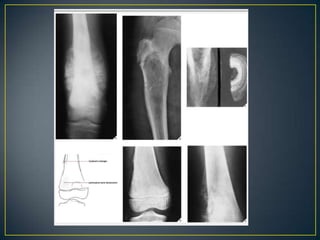

• IA – WELL DEFINED WITH SCLEROSIS

• IB- WELL DEFINED BUT NO SCLEROSIS

• IC- POORLY DEFINED

• The type of bone destruction caused by a tumor is

primarily related to the tumor growth rate.

• Geographic.

• Moth Eaten.

• Permeative.

• Categorized as uninterrupted or interrupted .

• The first type of reaction is marked by solid layers of

periosteal density, indicating a long-standing benign

process.

• The interrupted type of periosteal reaction suggests

malignancy or a highly aggressive nonmalignant process

and may present as a sunburst pattern, a lamellated

(onion-skin) pattern, a velvet pattern, or a Codman

triangle.